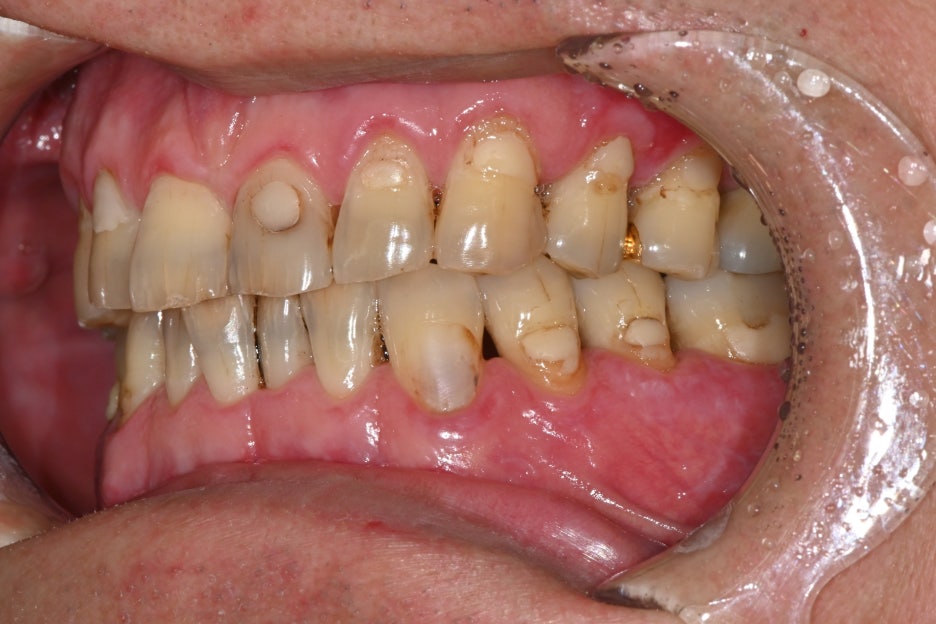

안녕하세요! 서울오브치과병원입니다. 오늘은 왼쪽 아래 어금니 임플란트 수술 사례를 소개해드리겠습니다. 환자분은 오래 전 발치 후 방치해 두었던 자리 때문에 씹는 불편함이 생겨 치료를 원하셨습니다. 초진 내원 당시 왼쪽 아래 어금니를 예전에 뽑았는데 요즘은 반대쪽으로만 씹다 보니 턱도 불편해요 환자분은 “왼쪽...

환자분은 오래 전 발치 후 방치해 두었던 자리 때문에

씹는 불편함이 생겨 치료를 원하셨습니다.

초진 내원 당시

왼쪽 아래

어금니를 예전에 뽑았는데

요즘은 반대쪽으로만 씹다 보니

턱도 불편해요

환자분은 “왼쪽 아래

요즘은 반대쪽으로만 씹다 보니 턱도 불편하다”는

주호소로 내원하셨습니다.

치아가 오랫동안 결손된 상태라 양쪽 균형이 맞지 않고

음식물이 자주 끼면서 잇몸도 불편했다고 말씀하셨습니다.